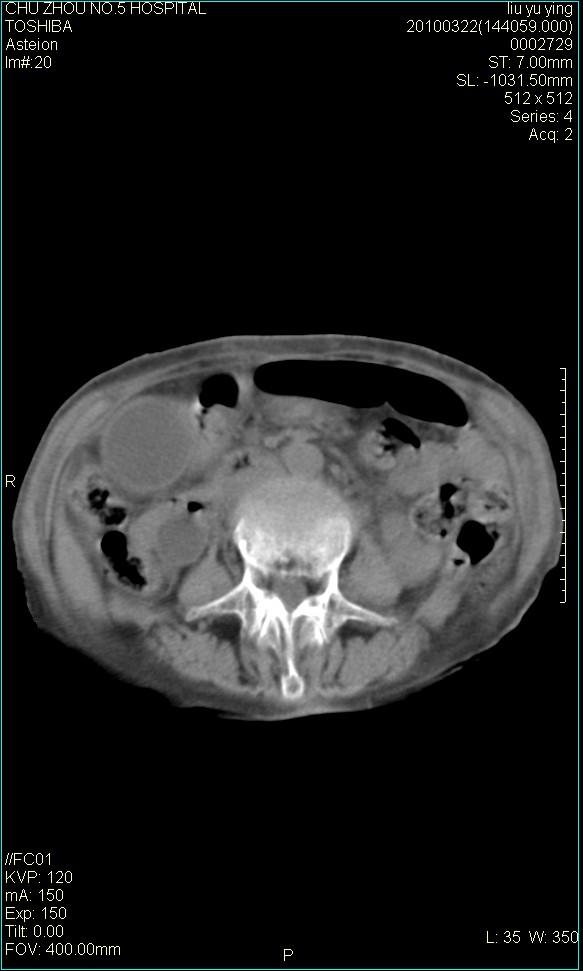

以下是引用科室第一人在2010-3-23 6:50:00的发言:[br]胆总管下段梗阻,多为肿瘤性病变,巨形胆囊,胆囊炎胆囊窝积液。[br]双侧胸腔积液,右降

以下是引用随光逐影在2010-3-23 8:12:00的发言:[br]1)胆系低位梗阻(肝内外胆管扩张,胆囊增大),原因待查。2)胆囊炎。3)双侧少量胸腔积液。4)降主动脉迂曲。